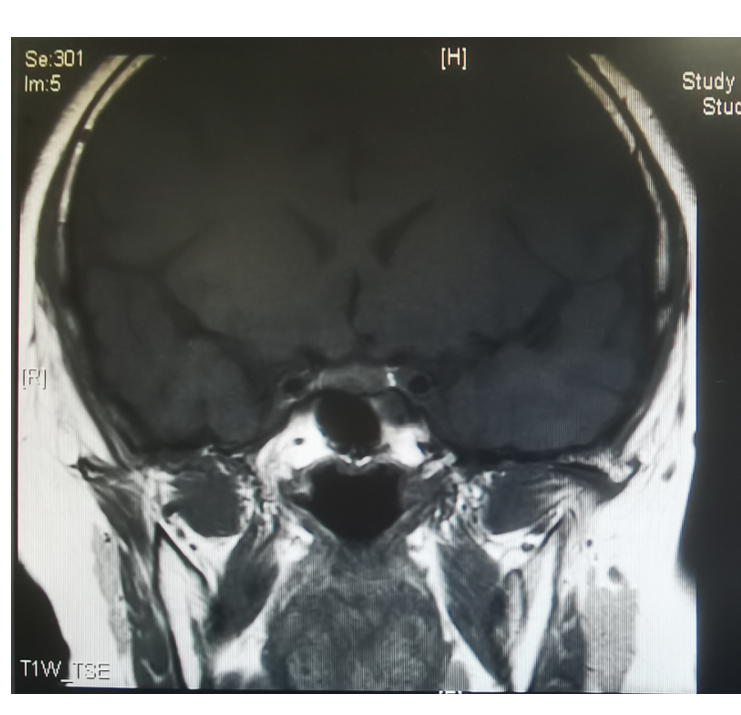

接诊飞飞的新桥医院内分泌科副主任隆敏副教授介绍,他们对飞飞进一步检查还发现他颈项部明显凸起、呈半月形,就像凸起的“水牛背”,孩子圆圆的小脸就像天上的“满月”。再结合激素检查和影像学检查,飞飞的促肾上腺皮质激素和皮质醇也有明显异常,颅内核磁发现脑垂体下方有一约4×5毫米大小结节影,因此专家们判断飞飞是因为脑垂体微腺瘤引起的库欣综合征。